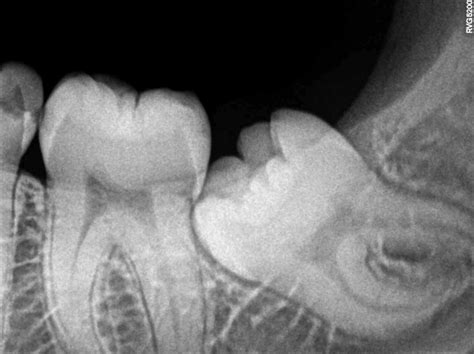

Dry socket is a common complication following tooth extractions, particularly wisdom teeth removal. It occurs when the blood clot that forms in the socket to protect the underlying bone and nerves is dislodged or dissolves prematurely. This exposure can lead to severe pain, bad breath, and a foul taste in the mouth. Dry socket images often depict the exposed bone and the inflamed tissue surrounding the socket, providing a visual representation of the condition.

• Visible Bone in the Socket: Dry socket images often show the exposed bone in the socket, which is a clear indicator of the condition.

• Exposed Bone: The presence of visible bone in the socket is a clear indication of dry socket.

In some cases, the dentist may take dry socket images to document the condition and monitor the healing process. These images can be useful for educational purposes and for tracking the progress of treatment.

Dry socket images can provide a visual representation of the condition, helping patients and dental professionals understand the signs and symptoms. These images typically show the exposed bone in the socket, inflamed tissue, and other characteristic features of dry socket. By examining dry socket images, patients can better recognize the condition and seek appropriate treatment.

Exposed Bone The presence of visible bone in the socket is a clear indicator of dry socket.

Inflamed Tissue The tissue surrounding the socket may appear red, swollen, and inflamed.